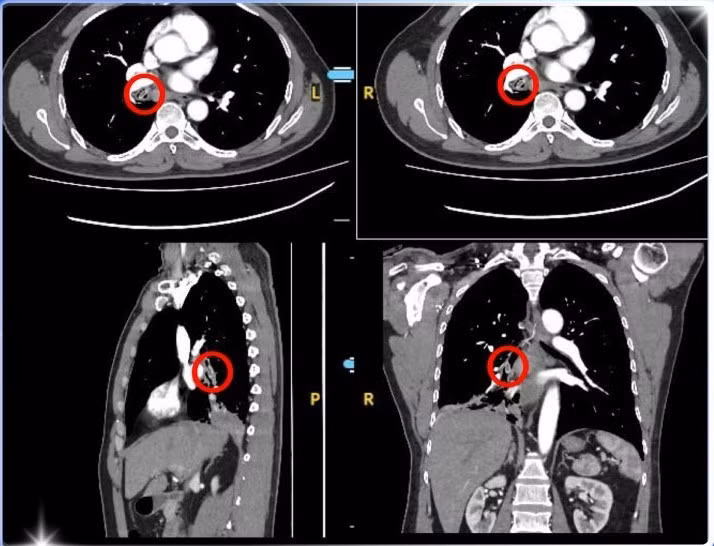

Tại phòng khám khoa Nội Tổng Quát, Bệnh viện Đa khoa Xuyên Á Long An, các bác sĩ tiến hành chụp CT scanner lồng ngực, kết quả cho thấy có dị vật hình bầu dục, kích thước khoảng 5,5 x 7,0 x 14,5 mm nằm trong phế quản gốc bên phải – nghi ngờ là một loại hạt trái cây mắc kẹt từ lâu.

ho-1-nam-4530.jpg

Hình ảnh CT lồng ngực xác định nguyên nhân của việc ho dai dẳng - Ảnh BVCC